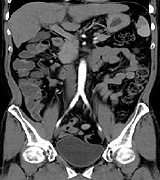

内脂肪測定

Fat Pointer

腹部CTを撮影したデーターより内臓脂肪値の計測ができます。

患者様に対してもわかりやすく色分けすることで、生活習慣病の診断に有用です。